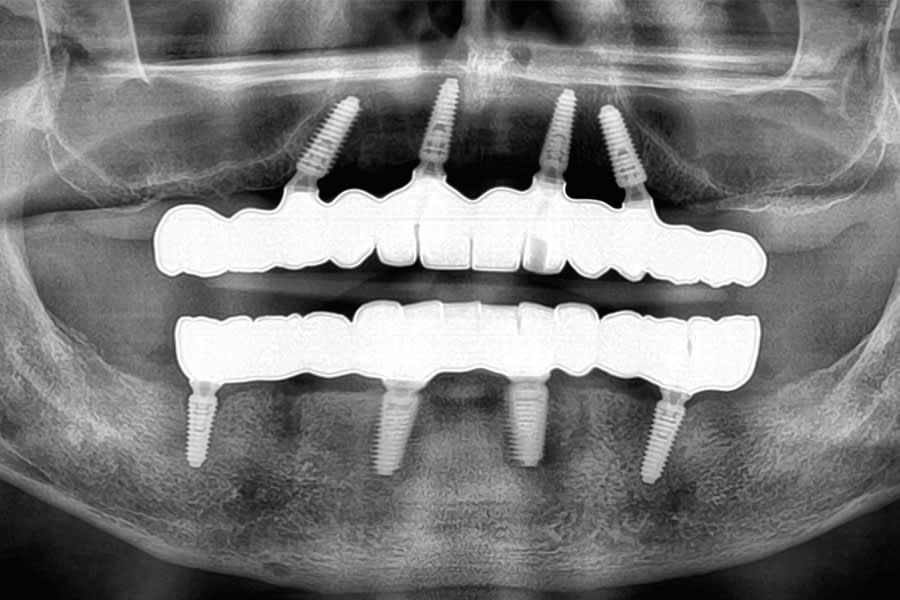

During surgery, flapless osteotomies were prepared under guided conditions. All implants achieved insertion torque values sufficient for immediate loading. Multi-unit abutments were connected, and the PMMA provisionals were relined intraorally, ensuring passive seating. Occlusion was carefully adjusted to light centric contacts and shallow lateral guidance, minimizing overload during early osseointegration (Figure 18 and Figure 19).

At delivery, the patient exhibited a harmonious smile, improved function, and increased confidence (Figure 31). Postoperative radiographs confirmed correct implant positioning (Figure 32). At the 6-month follow-up, peri-implant tissues remained stable, and no mechanical complications were reported.